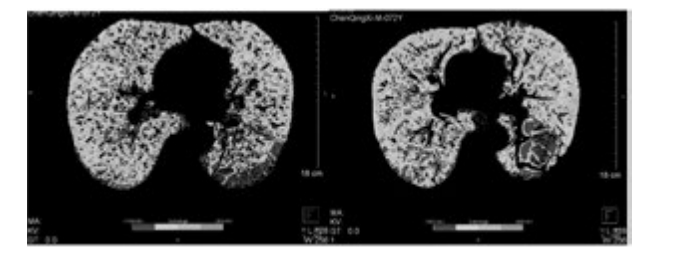

例1患者行干細胞移植前后肺部 CT 檢查

下圖為雙源CT肺實質分析軟件,深藍色表示CT值在-1000 至-951,治療后較治療前深藍色面積明顯縮小。

雙源CT肺實質分析軟件